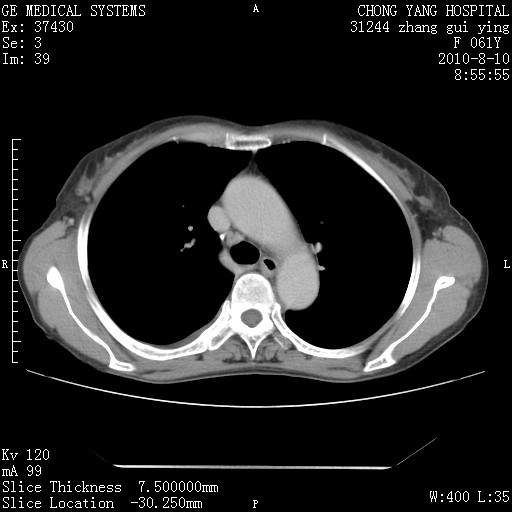

标题: CT28314:F61Y胸部增强,发热咳嗽一周入院,后面的为一周前平 [打印本页]

标题: CT28314:F61Y胸部增强,发热咳嗽一周入院,后面的为一周前平

1、支持考虑右侧中央型肺癌伴右肺中叶节段性不张及下叶支气管黏液痰栓    2、左肺上叶舌段感染。

支持3楼意见,还要考虑:纵隔及肺门淋巴结转移、右侧少量胸腔积液。

确切的说:1:右肺下叶中心型肺癌侵及中叶支气管并中叶不张,纵膈淋巴结转移。2:左肺舌叶炎症。3:右侧胸腔少量积液

块影平扫32hu,动静脉期62-70hu.